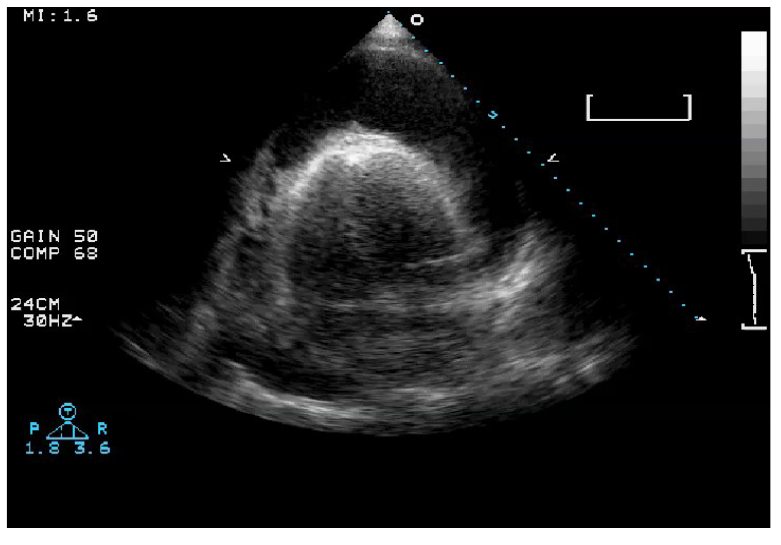

Q

What does this image represent?

A

Pericardiocentesis